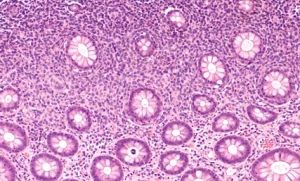

Biyopsi: Tanıyı kesinleştirmek için, şüpheli lenf bezinden bir doku örneği alınarak laboratuvar ortamında incelenir. Bu, lenfomanın türünü ve evresini belirlemek için oldukça önemlidir.